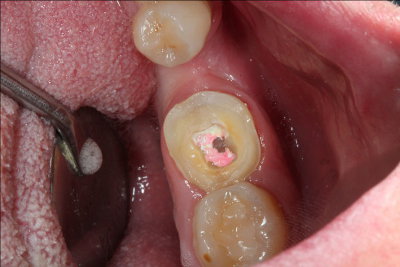

Caso práctico de endodoncia. Clínica Dental Fernández León Caso práctico de endodoncia. Clínica Dental Fernández León